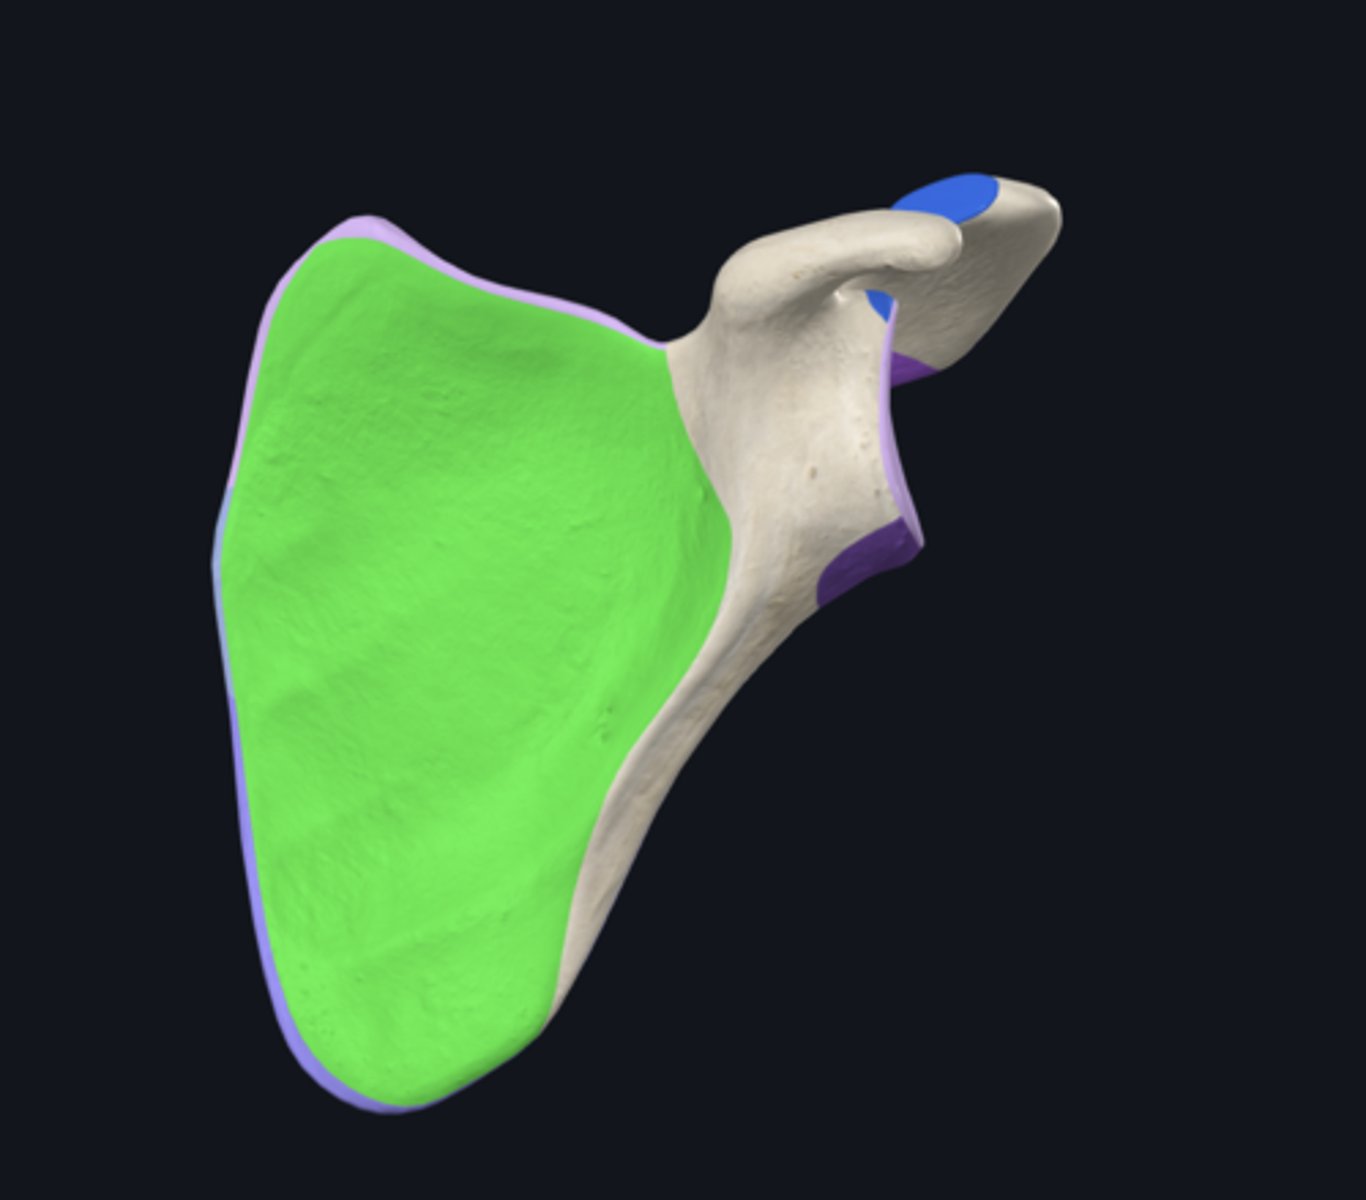

body of scapula

costal surface of scapula

posterior surface of scapula

infraspinous fossa

subscapular fossa

supraspinous fossa